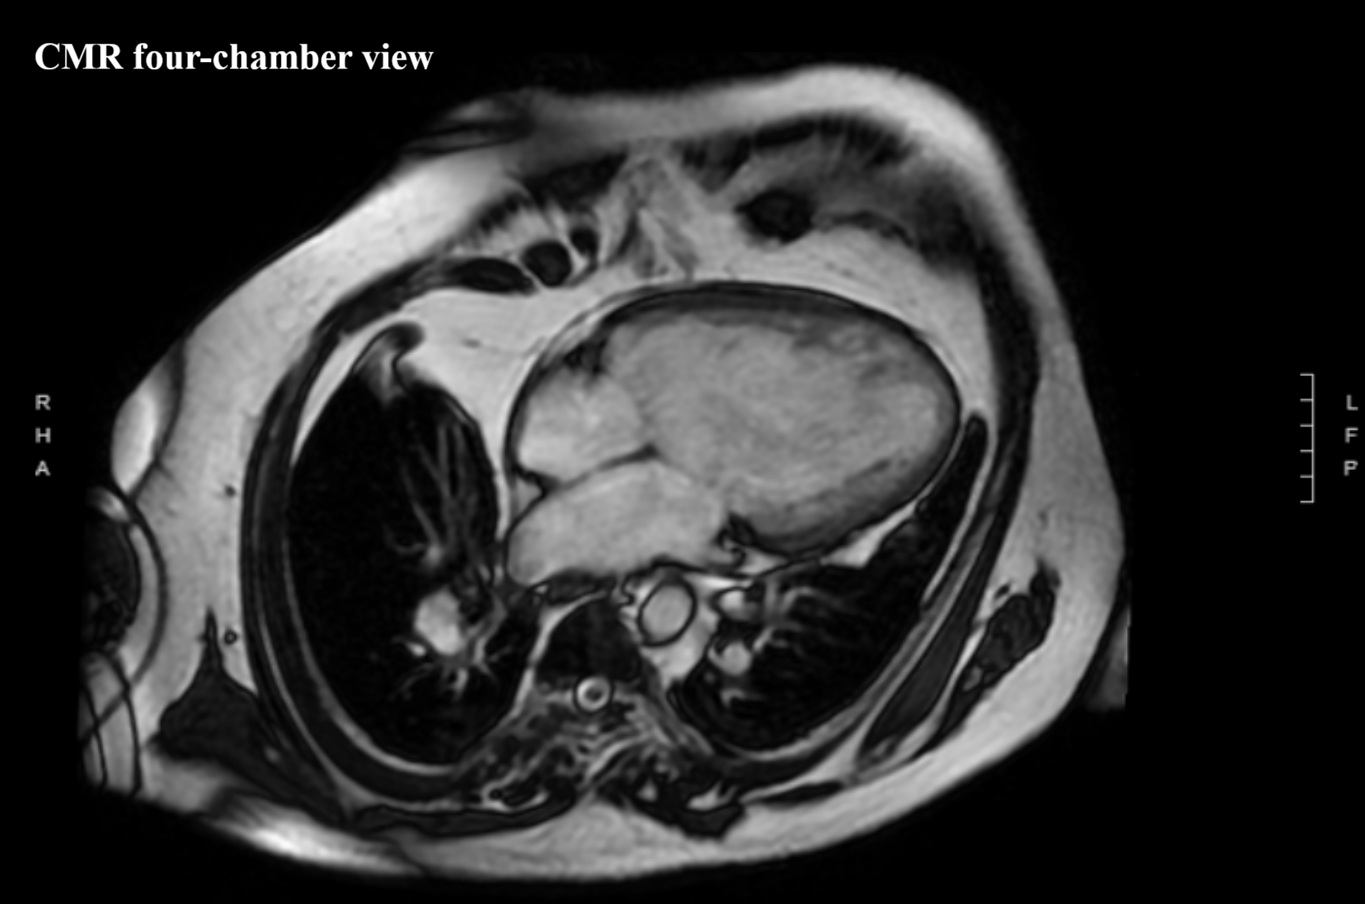

We report a 61-year-old man with unrepaired single-ventricle physiology (double inlet left ventricle, mesocardia, malposed great vessels) and stable chronic cyanosis (baseline SpO2 80–85%). In the absence of a “protective” pulmonary stenosis, lifelong high pulmonary flow and pressure led to pulmonary vascular remodeling and increased resistance, resulting in severe pulmonary arterial hypertension (PAH) with Eisenmenger-type physiology; the single ventricular pump is highly preload-, cardiac rhythm-, and systemic pressure–dependent. The course is complicated by acquired ischemic heart disease: an anterior acute coronary syndrome in 2015 in the setting of anomalous coronaries and supply–demand mismatch. Cardiac MRI showed severe dominant-ventricle dilation, EF ~33%, and antero-apical subendocardial late gadolinium enhancement. Right-heart catheterization confirmed severe PAH with PAP 120/22 mmHg (mean 55), PAWP 9 mmHg and PVR 6.2 WU, supporting initiation of triple PAH therapy (macitentan, sildenafil, selexipag) with close monitoring of systemic pressure and volume status. Clinical decompensations were triggered by atrial fibrillation or atrial tachycardia with high ventricular response, managed with rhythm and/or rate control (amiodarone, digoxin, cautious beta-blocker titration) and tailored decongestion. Non-invasive ventilation with positive pressures (BiLevel) was set conservatively given the effects of intrathoracic pressure on venous return and pulmonary circulation. Long survivors with DILV in natural history are exceedingly rare and appear to cluster into two phenotypes: “balanced” circulations with restricted pulmonary flow, and exceptional cases without protection who develop pulmonary vasculopathy. This patient belongs to the latter and is notable for triple PAH therapy; depressed systolic function may have mitigated pulmonary flow overload, contributing to a fragile equilibrium. Arrhythmic/sudden-death risk stratification in a single ventricle with scar led to ICD counselling, which the patient refused. Unrepaired DILV reaching the sixth decade with severe PAH is exceptional; management should remain physiology-driven.